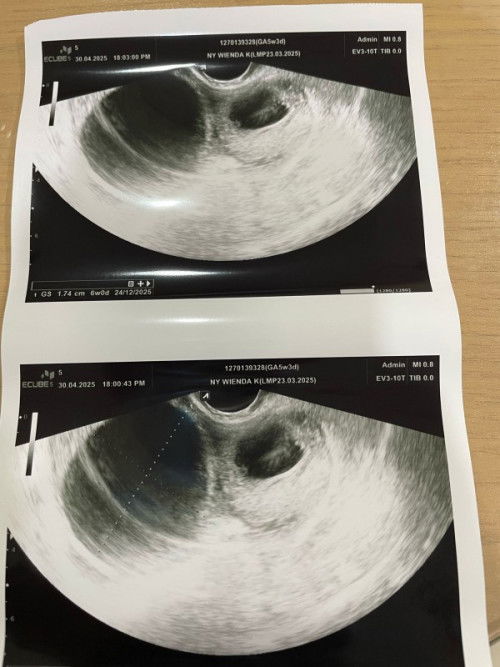

Kista saat hamil 5 minggu dan pendarahan terus apa aman untuk kandunhan.. Perlu pencerahan moms

sama.. sya juga ada kista tp diluar rahim.. usia kehamilan 5minggu. tp tidak ada pendarahan.. kata dokter kista bisa mengecil/membesar. jadi harus rutin periksa. dan sebaiknya kita jaga pola makan dan hidup sehat bun.

aku juga kmren usg pas kehamilan 5 week, ada kista juga kak trus usg ke 2 pas 7 week alhamdulilah kistanya mengecil aku juga smpet ngflek

sama banget bun. hari ini aku br tau kalau hamil, langsng USG untuk mastiin malah ada kista 5 cm :(